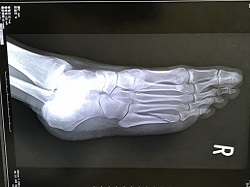

交差点で対向車と衝突してむち打ちと足の複雑骨折の診断を受け、足の骨折で2カ月入院し、その間、むち打ちの治療も行いました。

退院後も足に痛みがあったが、足の骨折の治療をした外科医は、骨折は治っているので、症状固定をして後遺障害の認定を受けるよう勧められました。

むち打ちの他に、骨折などの重傷を負って後遺症が残った場合、むち打ち以外の怪我について症状固定をしても、損害賠償請求で問題は起こりません。

ただ、症状固定日が後遺障害を計算する起算日となるので、むち打ちについても後遺障害が認められた場合、骨折と怪我で後遺障害の起算日が変わることは理解しておきましょう。